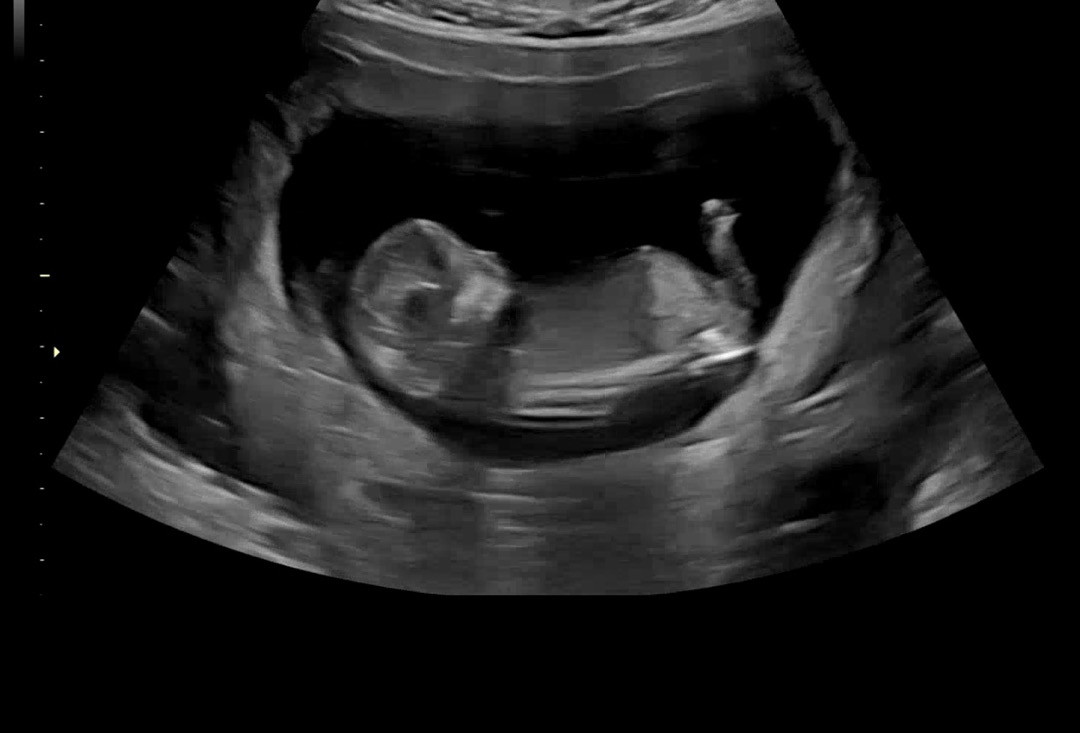

12์ฃผ์ฐจ์ธ๋ฐ ์ฑ๋ณ ๋๋ฌด๋๋ฌด ๊ถ๊ธํด์ ์ฌ๋ ค๋ด ๋๋ค ํฌํ๋ถํ๋๋ ค์ฉ๐ค

์ฐ๋ฆฌ ์๊ธฐ ์ฑ๋ณ์ด ๊ถ๊ธํ๋ค๋ฉด?

์ด์ํ ์ฌ์ง์ ์ฌ๋ฆฌ๋ฉด AI๊ฐ ๋ฌด๋ฃ๋ก ์์ธกํด์ค์